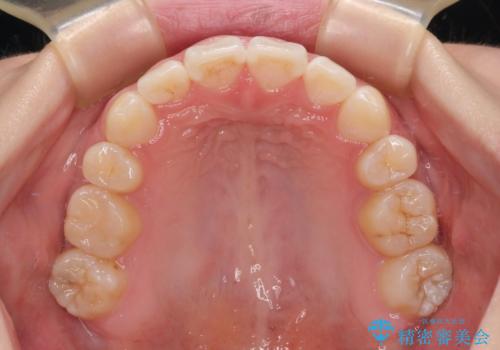

上下非接触の前歯 口元の突出感を改善する抜歯矯正

舌のトレーニングをしっかりと行ってくださり、1年半という非常に短い期間で仕上げることができました。

舌の突出癖により上下の前歯は非接触となっている状態でした。

舌のトレーニングを行わないと上下前歯の接触達成は困難であるため、トレーニングをしっかりと行っていただきながら、治療を進めて行くこととしました。